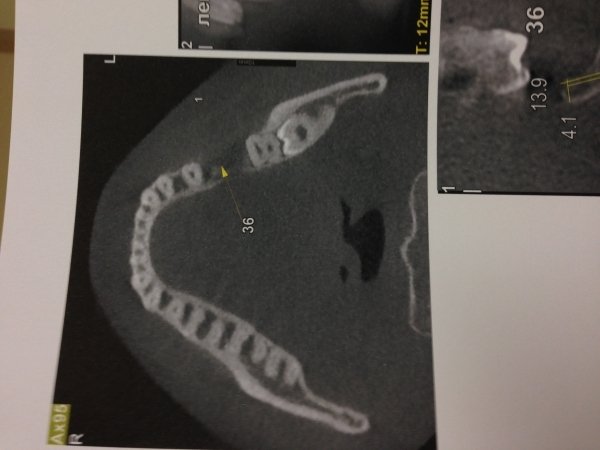

Удален шестой зуб резорциновый. Сделана мной ортопантомограмма. На снимке видно, что костная ткань, где были корни зуба, не восстановилась.

Подскажите, пожалуйста, срок восстановления костной ткани и что может послужить не восстановлению моей костной ткани? Возможна ли в дальнейшем имплантация?

Срок восстановления костной ткани зависит от степени травматичности удаления, но как правило, от 3 - 6 месяцев. Выложите мне снимок, я вам все расскажу.